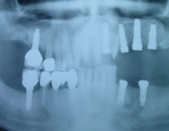

The placement of Implants involves a short surgical procedure, which requires placing a screw-like structure into the jaw bone. The Bone and Implant need to integrate, this takes about 3-4 months, the Implant Fixture and final Implant Crown can be fitted.

The Mechanical aspect of the surgery can be seen in the accompanying video link: Single tooth replacement Video